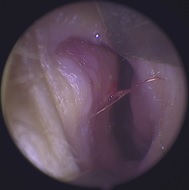

這是一個小孩鼻部流鼻血的照片,小朋友過敏性鼻炎常會忍不住抓鼻孔、揉鼻子造成鼻黏膜受傷,圖中左側是鼻中隔,右側是鼻甲骨及腫脹的鼻黏膜,圖中可以看到在鼻中隔的位置有一個出血點,這是鼻子最容易出血的位置,大約就在鼻孔進去不到1公分的距離,不管是揉鼻子或是挖鼻孔都是容易在這位置製造傷口。